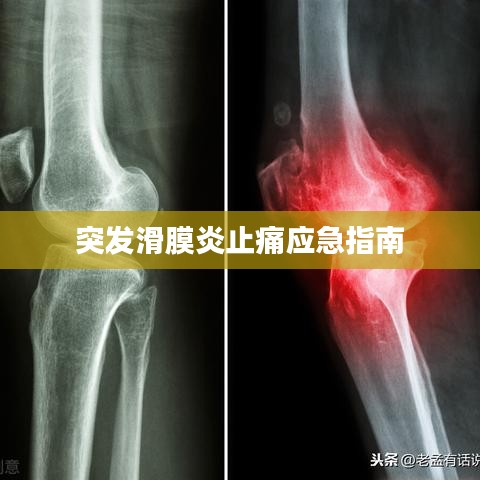

突发滑膜炎概述

突发滑膜炎是一种常见的关节疾病,主要表现为关节肿胀、疼痛、活动受限等症状,在发病初期,患者往往遭受剧烈的疼痛,严重影响了日常生活和工作,了解如何止痛,对于缓解患者痛苦、提高生活质量具有重要意义。